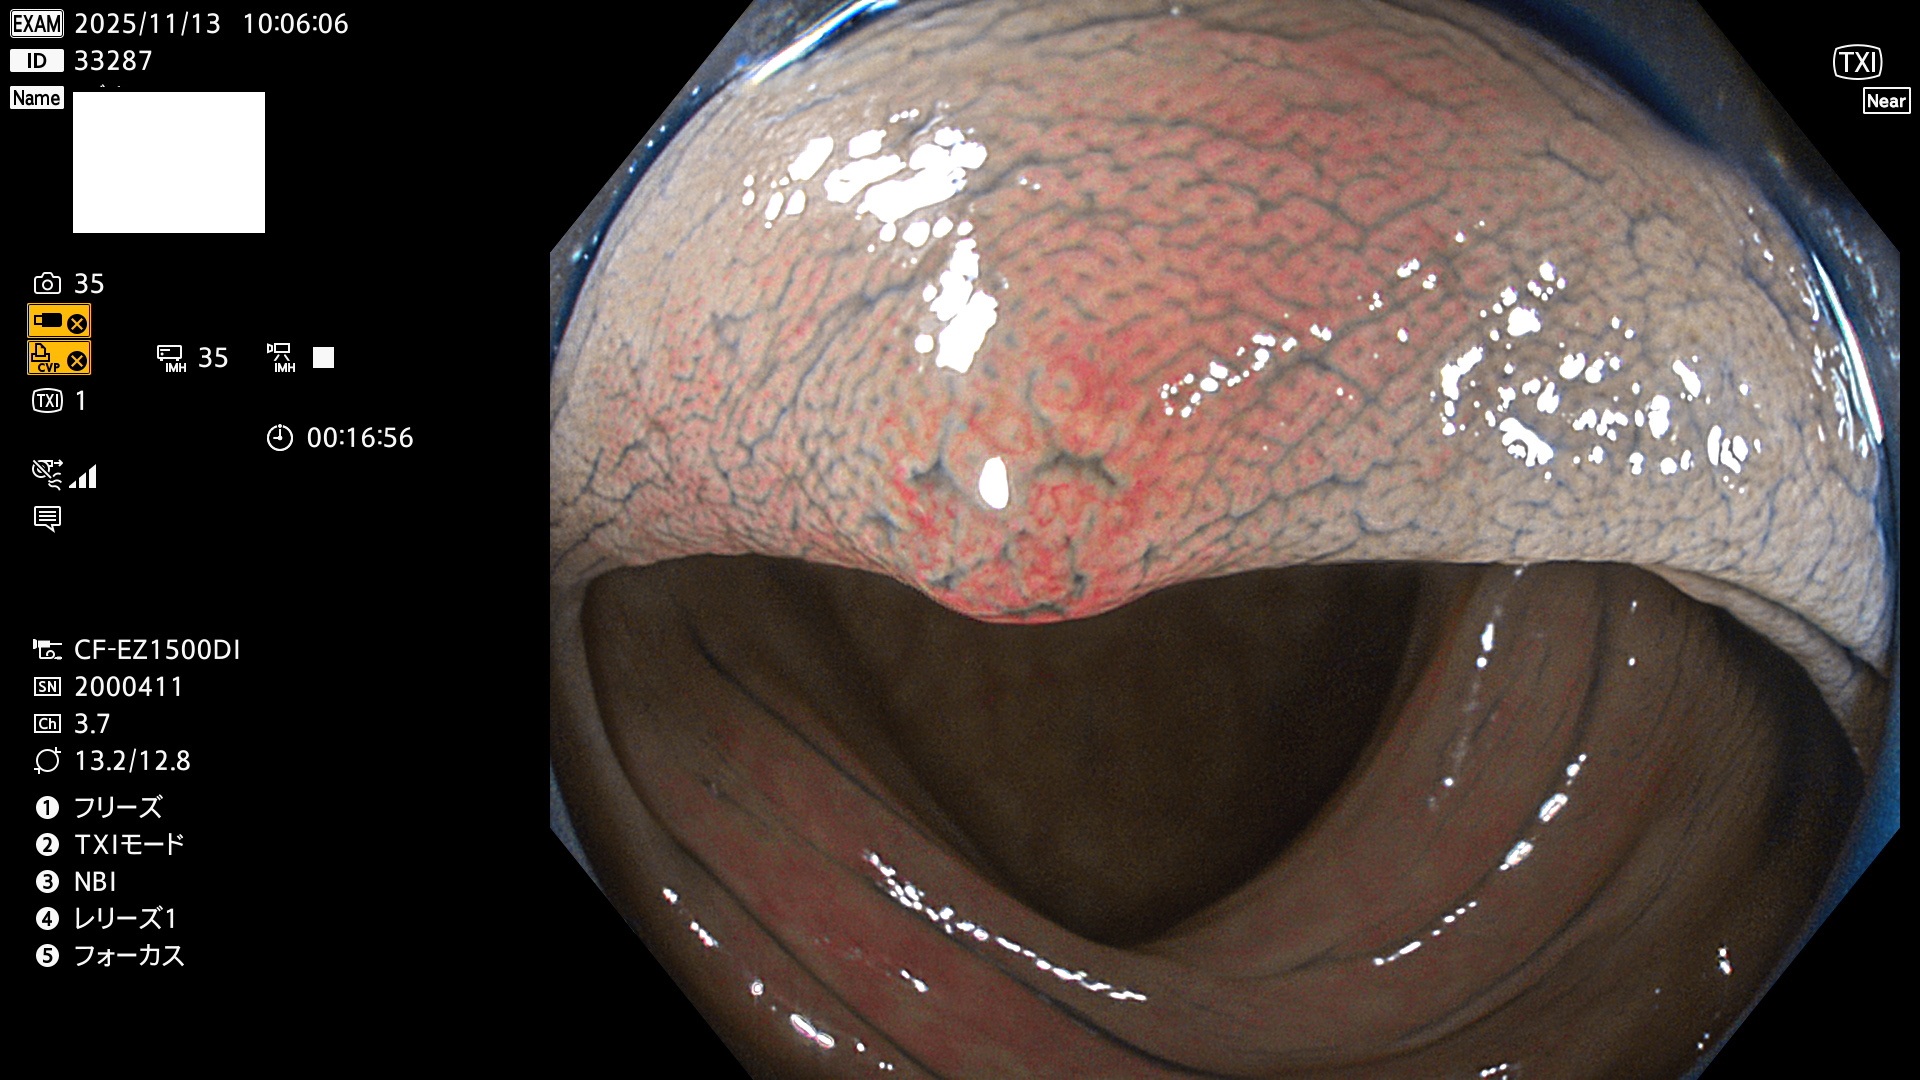

完全に平坦な物をUb、陥凹している物をUcと呼びます。Ubは認識が困難で、Ucはびらん(炎症)と紛らわしいために見落とされやすく、「内視鏡後・大腸癌」の原因になります。

2025年11月13日〜11月16日の4日間(40件)で4個 (Uc_ADR=4個/40人=10%)